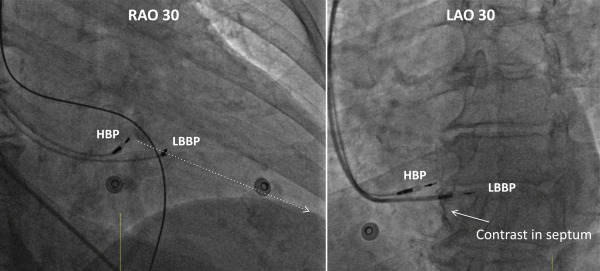

Plusieurs stimulations alternatives ont dès lors été testées, dont celle de la branche gauche du faisceau de His (ou faisceau atrioventriculaire qui est un faisceau de cellules musculaires cardiaques spécialisées dans la conduction électrique). Cette technique (SBG, Stimulation de la Branche Gauche ou en anglais LBBAP pour Left bundle branch area pacing) implique de stimuler le système de conduction du cœur plus distalement, ce qui permet une activation rapide et homogène du ventricule gauche et d’éviter l’apparition d’une dyssynchronie ventriculaire lors de la stimulation.

Les 4 procédures d’implantation ont été réalisées avec succès par le Dr Cynthia Barbraud, cette technique permettant ainsi une stimulation ventriculaire avec des QRS fins, dans le but d'éviter l'asynchronisme lié à la stimulation du ventricule droit. Et une belle collaboration se développe dans ce cadre avec l'UZ Gent et la Clinique Saint Pierre Ottignies